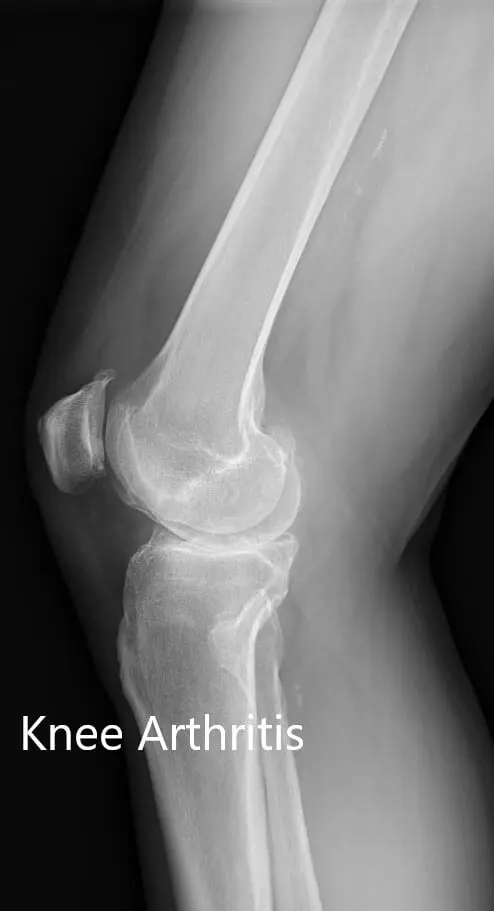

Imaging study revealed severe osteoarthritis of both knees. Considering her lifestyle limiting knee pain, she was offered bilateral custom total knee replacement. Risks, benefits, and alternatives were discussed thoroughly with her and her daughter. She agreed to go ahead with the surgery.

Preoperative X-ray showing the lateral view of the left and the right knee joint